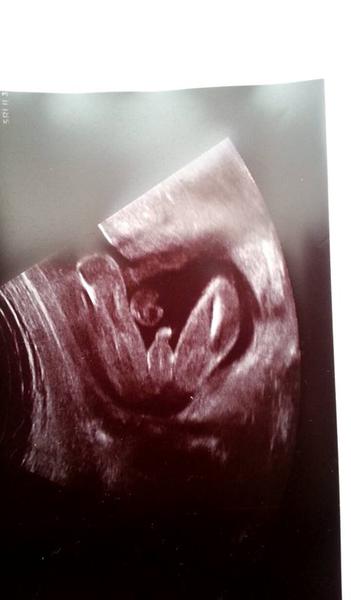

No prave něco tam visí ale co to je ze.Jinac foto je foceno tak ze dole je zadeček a nahoru vedou nozky

nejak se ve fotce neorientuju 😒 ...tady podle toho by to mel byt kluk nebo holka ?

@zuziry : na tohle ti rekla holcicku ?? 🙊tak uvidíš třeba ji met budeš. ... já tam vidím výstavního pindika...i s kuličkami,ale jestli ti to řekla tak třeba holčičku mít budeš 😉ten 20 týden je docela přesný pokud jsou nožičky takhle zepředu. A kdyby to byl kluk,tak nevěš hlavu,ja tenkrát i plakala a dnes bych ho nevymenila za nic na světě, mám totiž také 3kluky...😉

@satynka Mně je pohlaví jedno 🙂. No ale jak jsem doma koukala na tu fotku, tak se mi taky zdá že to je kluk. Leda že by to byl kousek bříška, ale to se mi nezdá tak symetrické ( vyznačím to )...

Já tam taky vidím pindíka 😉 .